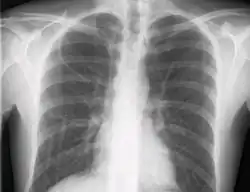

Во многих случаях введение катетера осуществляется по методике Сельдингера: сквозь иглу проводится проводник, далее игла удаляется. Далее по проводнику вводится дилататор для того, чтобы немного расширить канал для введения мягкого катетера. На завершающем этапе по проводнику вводится сам центральный венозный катетер и проводник удаляется. Производится аспирация из всех просветов катетера (чтобы убедиться, что они расположены в просвете вены), после чего катетер необходимо промыть. Как правило, по завершении постановки катетера проводится рентгенограмма грудной клетки, для подтверждения правильного положения кончика катетера в верхней полой вене, а также для исключения пневмоторакса на стороне пункции. Системы васкулярного позиционирования также помогают определить область нахождения кончика катетера при введении без необходимости применения рентгена, но эта техника пока не является стандартной.